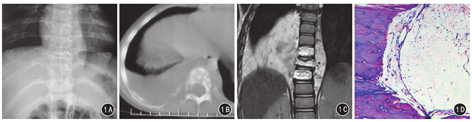

患儿女,3岁,因"间断性低热伴盗汗2个月"就诊。2个月前患儿无明显原因出现间断性低热伴盗汗,11 d前出现低热、头晕伴喷射性呕吐就诊于当地医院,诊断为右侧胸腔积液,经对症治疗好转;5天前胸部CT示:右侧肋骨及胸椎多发破坏,右侧胸腔积液。2010年6月22日入住我院。体格检查:体温37.2 ℃,精神可,右下肺叩诊浊音,右下肺呼吸音减低,未闻及干湿性啰音;胸腰段椎体轻度侧凸,T8~10椎体水平轻度叩击痛;四肢无畸形,活动、感觉未见明显异常。实验室检查:结核菌素试验阴性,红细胞沉降率6 mm/1 h,骨髓瘤检查及肿瘤六项检查未见异常,胸腔积液培养无细菌生长,支原体抗体及EB病毒-DNA阴性,血红蛋白101 g/L,碱性磷酸酶193 U/L(正常值15~130 U/L)。超声检查示右侧胸腔内约4.3 cm×4.2 cm的不均匀回声团块。胸椎X线片示T9椎体及右侧第9后肋不规则骨质破坏,T8、T10椎体及右侧第8、10后肋似有骨质破坏(图1A)。CT平扫椎体、右侧肋骨可见不规则的骨质破坏区,边缘模糊,密度不均匀,椎旁及后纵隔软组织肿胀,右侧胸腔内可见半月形的偏高密度(图1B)。MRI表现:矢状位T1WI示T8、T10椎体呈不均匀的高信号,T9椎体呈不均匀低信号;矢状位T2WI示T8~10呈高信号;矢状位脂肪抑制序列示T8~10椎体呈不均匀的低信号,T9椎体呈不均匀高信号;冠状位及轴位T2WI示T8~10椎体、右侧破坏肋骨、椎旁及后纵隔肿胀的软组织及右侧胸腔内病变呈不均匀高信号(图1C)。发射型计算机断层成像示T8、T10椎体局部放射性摄取稍减低。2010年7月5日患儿于胸外科行右侧第9后肋切除活检术,术中见右侧第9后肋呈多囊状骨质破坏,骨髓腔与胸腔相通,并有乳白色液体流出,切除右侧第9病变肋骨约7 cm送病理检查;吸除右侧胸腔积液约600 mL,见右侧胸腔有膜性粘连。术后病理检查显示:病变段肋骨内呈蜂窝状骨质破坏,皮质变薄呈蛋壳样,骨内囊腔间隔厚薄不均匀,其内无软组织;镜下见骨小梁间大小不等的薄壁扩张的淋巴管,管壁衬覆扁平内皮细胞,管壁和管腔内可见淋巴细胞和蛋白性液体(图1D)。病理诊断:骨淋巴管瘤。术后患儿症状有缓解,出院半年后失访。